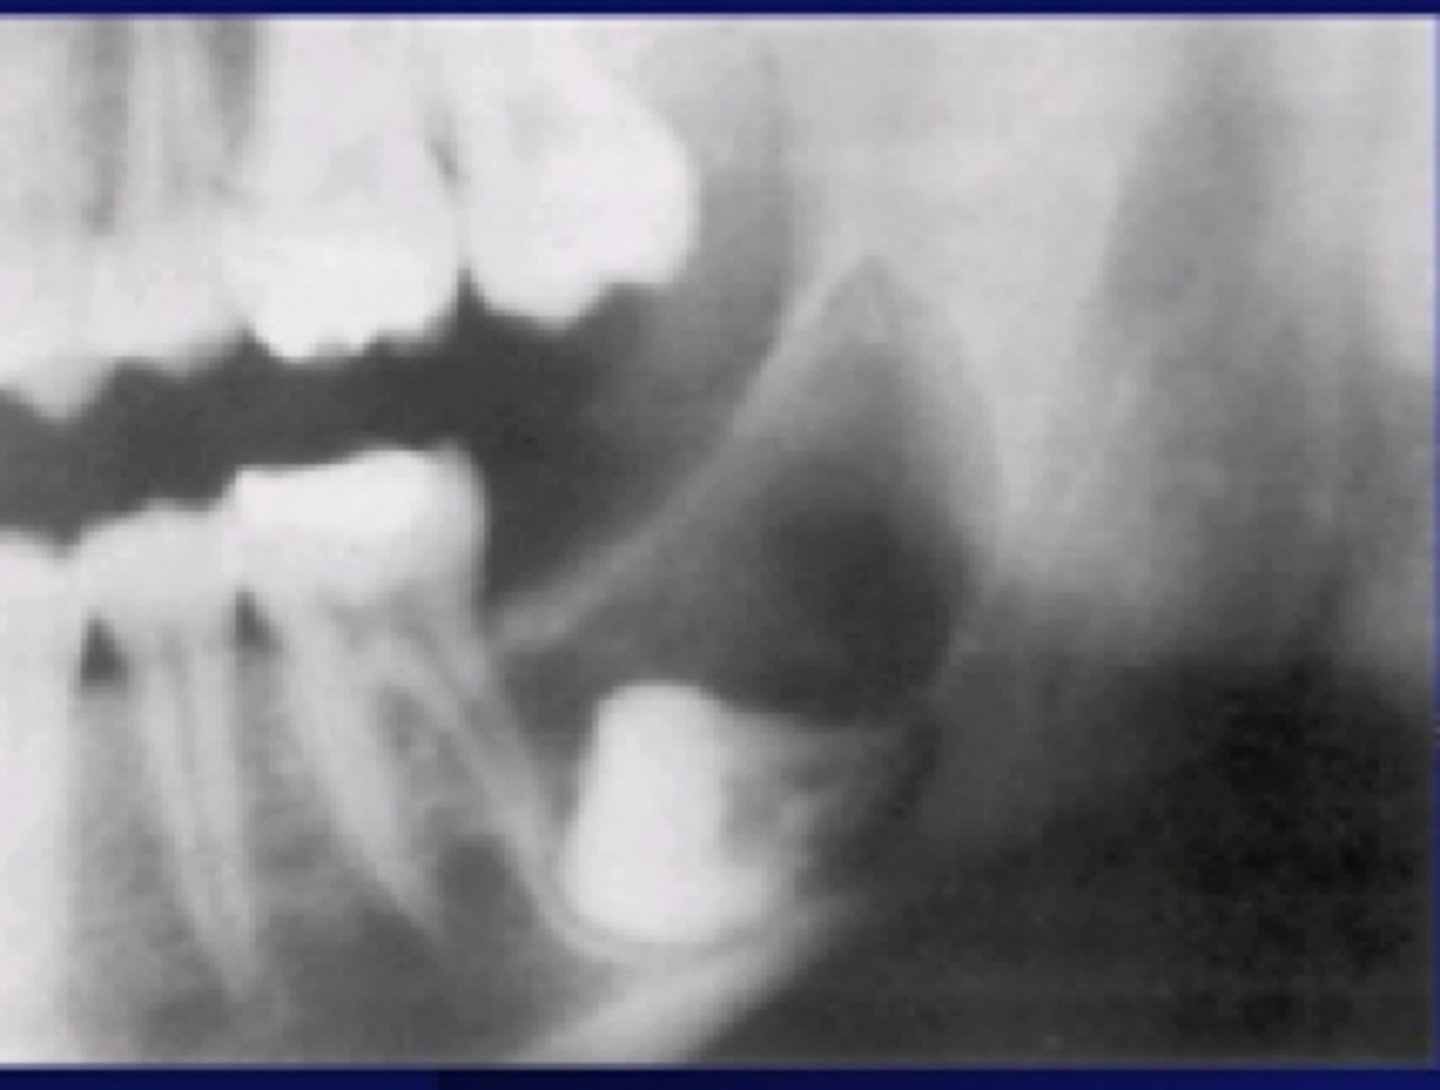

Radiographic Signs of Ameloblastoma

cortical expansion, thinning, and/or erosion

root resorption common

80% mandible

Ameloblastomas are notoriously ___locular

multi